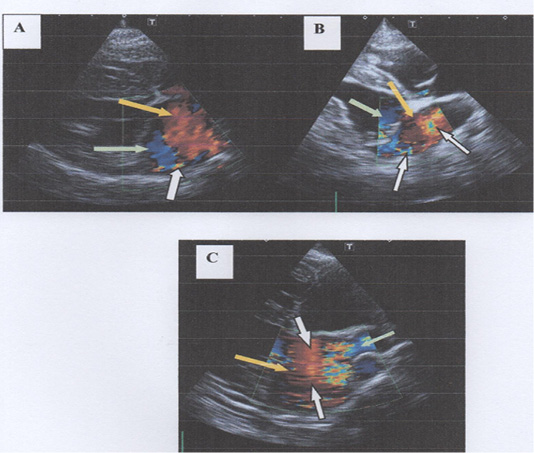

Degree of mitral regurgitation (MR) into left atrium at right parasternal long axis four chamber view using Doppler echocardiography. In 3-A, there is mild mitral regurgitation in to left atrium with mild baseline colour scale is shifted and presence of less than 10% of colour aliasing. In 3-B, there is moderate mitral regurgitation with moderate baseline colour is shifted and presence of 50% of colour aliasing. In 3-C, there is severe mitral regurgitation with severe baseline colour scale is shifted and presence of more than 50% of colour aliasing. Note: Yellow arrows show shades of red indicates the bloods flow towards transducer; Green arrows show shades of blue indicates the blood flow directed away from transducer; White arrows show the presence of colour aliasing).